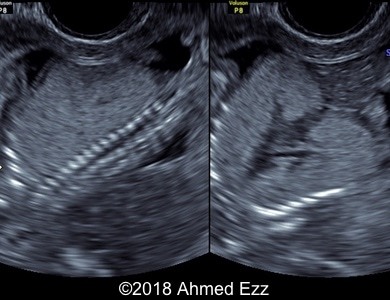

Images 1-5: 2D transabdominal and transvaginal ultrasound images of the fetus showing the anhydramnios, enlarged and echogenic lungs with eversion of diaphragms, compression of the heart and flattened adrenal glands.

Images 6: tomographic ultrasound image showing enlarged and echogenic lungs, eversion of diaphragm, compressed heart, consistent with laryngeal atresia.

-Anhydramnios

-Bilateral enlarged echogenic lungs

-Eversion of diaphragm

-Fluid-filled bronchi

-Compression of heart